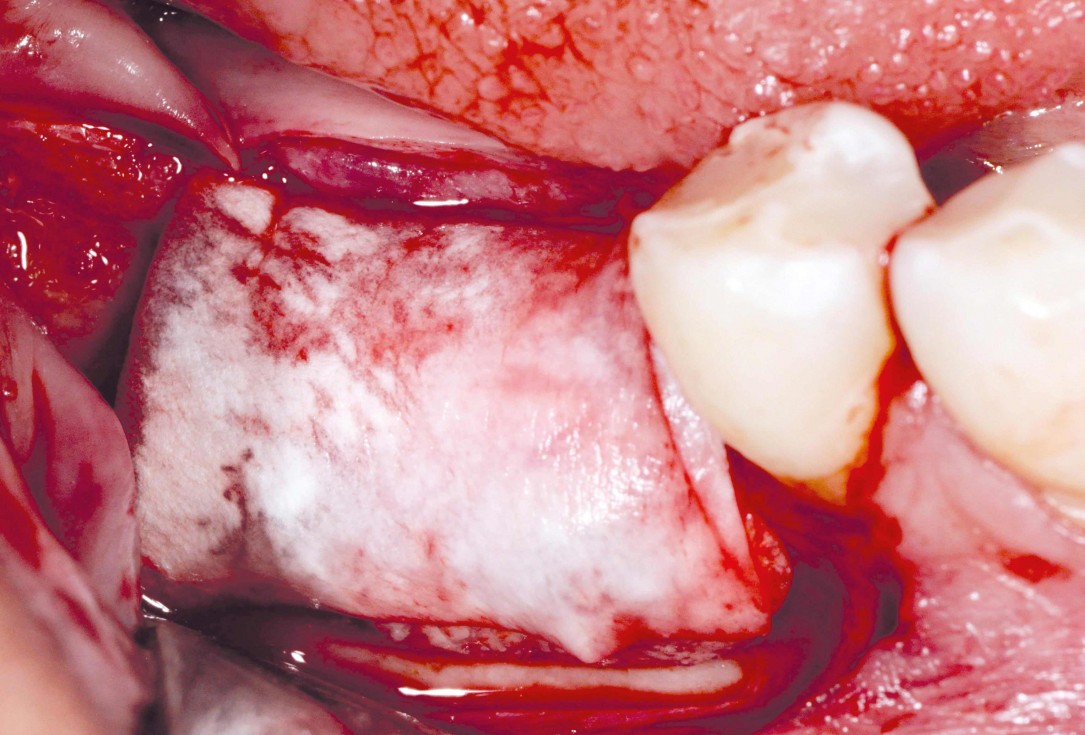

Initial clinical situation: Bone defect in the upper right maxilla (teeth #14-16)